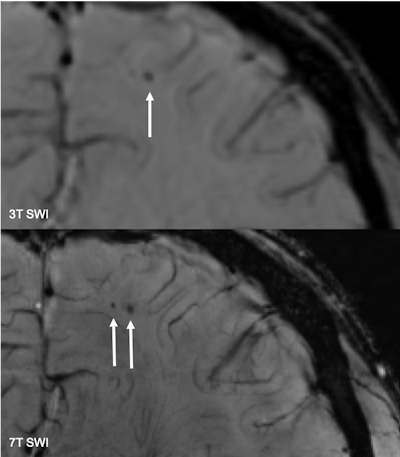

The duo observed a total of three cerebral microbleeds in three different American football players on the 3-tesla SWI. With 7-tesla SWI, one of these cerebral microbleeds was confirmed, as well as two smaller adjacent cerebral microbleeds. In the control group, as one might expect, no microbleeds were found.

SWI at 7 tesla also clarified the other two suspected cerebral microbleeds seen on 3-tesla MRI in the other two American football players by distinguishing them as atypical small intracerebral veins.